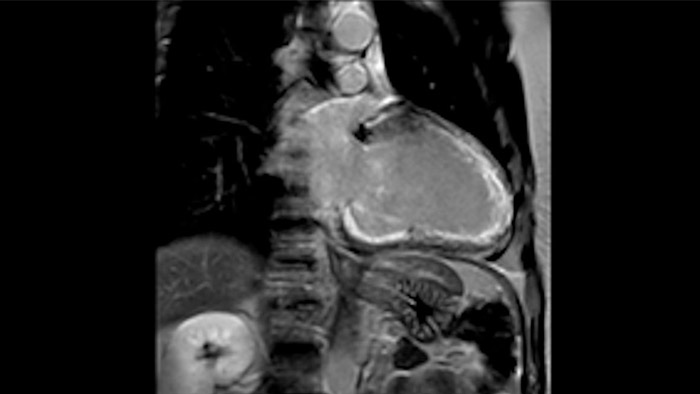

A utilidade do diagnóstico e prognóstico da RM cardíaca está a aumentar. Avalie a anatomia e função do coração utilizando aquisições cine, adquira informações sobre a perfusão e viabilidade do tecido cardíaco, visualize potenciais edemas com sequência de sangue escuro, aceda e quantifique mesmo a caracterização do tecido com a CardiacQuant.